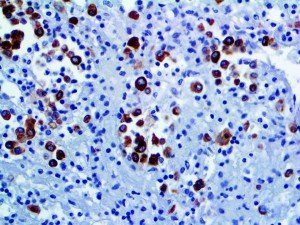

It is the ICU physician who is most likely to witness one of the deadliest manifestations of the abnormal immunological response, the cytokine storm syndrome (CSS). This response is also referred to by some as the cytokine release syndrome (CRS). CSS is characterized by continuous activation and expansion of macrophage and lymphocyte populations, which secrete large amounts of cytokines, causing the cytokine storm. This massive cytokine release is akin to hemophagocytic lymphohistiocytosis (HLH) disease, a syndrome characterized by initial unchecked and persistent activation of cytotoxic T lymphocytes and NK cells.

Clinical and laboratory manifestations of HLH include fever, enlarged liver and/or spleen, neurologic dysfunction, coagulopathy, liver dysfunction, cytopenias (i.e., low levels of erythrocytes, leukocytes, and/or platelets), hypertriglyceridemia, hyperferritinemia, hemophagocytosis, and eventually diminished NK cell activity as the immune system becomes progressively paralyzed. HLH can be familial (primary HLH) or secondary to another disease process (sHLH), such as rheumatic disease, in which it is referred to as macrophage activation syndrome (MAS, characterized by elevated ferritin).